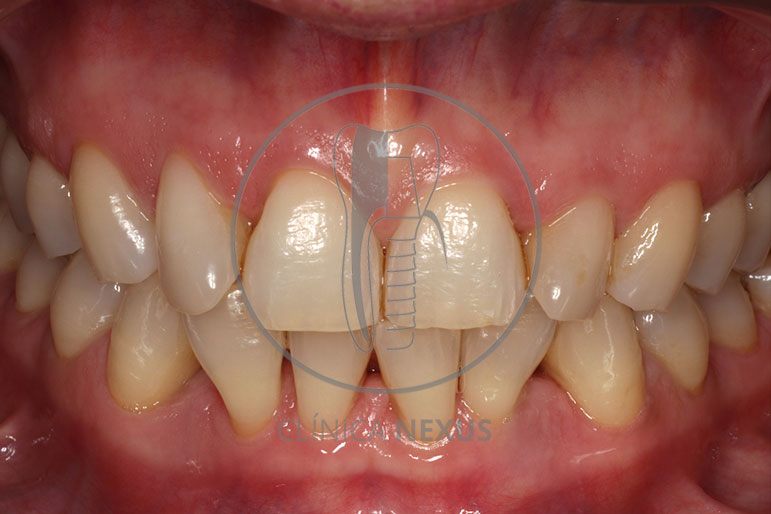

Tratamiento de defectos periodontales infraóseos en sector antero-inferior empleando gel de amelogeninas (Emdogain®) en combinación con un aloinjerto óseo (Biobank®). Paciente de 64 años, sin problemas médicos de relevancia, que presenta una periodontitis leve generalizada, pero asociada a presencia de defectos óseos verticales profundos a nivel de los espacios interdentales entre los caninos y los incisivos laterales inferiores. Tras la pertinente fase higiénica, se llevó a cabo una cirugía periodontal regenerativa, en la que, tras eliminar el cálculo subgingival (factor causal), se empleó una combinación de amelogeninas con un aloinjerto, para promover la regeneración tisular del periodonto perdido. Las imágenes clínicas y radiológicas, al año de seguimiento, reflejan un resultado terapéutico óptimo, con regeneración completa del tejido periodontal y mejora del pronóstico de los dientes involucrados.